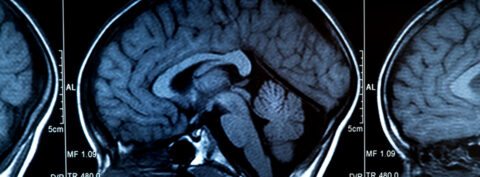

La dopamina se produce principalmente en las neuronas dopaminérgicas localizadas en el tronco del encéfalo y en hipotálamo. Por su parte, la serotonina se produce principalmente en el tronco del encéfalo, aunque se almacena en su mayor parte en las células del tracto gastrointestinal y en las plaquetas.

La dopamina es un neurotransmisor asociado principalmente con funciones cerebrales como la coordinación de los movimientos, la memoria, la toma de decisiones, la motivación, el aprendizaje y la recompensa, mecanismo de nuestro cerebro que nos refuerza a repetir una conducta. Además, influye en numerosas funciones fuera del cerebro como la motilidad gastrointestinal, la liberación de hormonas, la regulación de la presión arterial e incluso en la actividad de las células del sistema inmune.

La serotonina es un neurotransmisor que desempeña un papel importante en la regulación del estado de ánimo, el sueño, el apetito y las funciones cognitivas. A diferencia de la dopamina, la serotonina está más relacionada con la estabilidad emocional, la sensación de felicidad y el control del apetito y el sueño. También interviene, como la dopamina, en procesos de aprendizaje y memoria.